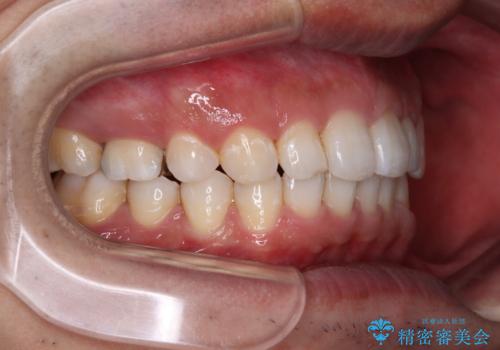

- 前歯の隙間を気にして来院された患者様です。

下顎前歯が見えなくなるくらいに深い咬み合わせであり、さらに上顎の正中が開くほど下の前歯が突き上げている状態でした。

奥歯は手前に倒れてしまっているため、後方に起き上がらせることで深い咬み合わせ・ディープバイトを改善する必要があります。

元々隙間の空いていた上顎の正中は、後戻りのリスクが高いため、下顎前歯同様ワイヤー固定を行いました。